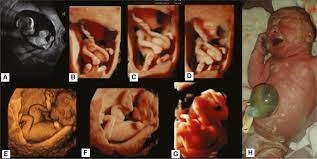

Of the many defects 3D 4D ultrasound has been useful in evaluating the skeletal and cardiovascular systems in fetuses with this condition. But keeping tabs on your babys growth can be a good thing and knowledge is power. By combining the results of the two parts of the test it is possible to identify if a pregnant woman is at increased risk of having a baby with Down syndrome.

A normal heart rate for a baby ranges from 120 to 160 beats per minute. By itself the test does not tell. These include increased nuchal translucency short femurs and abnormalities of the heart bowel and kidneys.

An ultrasound can detect fluid at the back of a fetuss neck which sometimes indicates Down syndrome. Ultrasound alone cannot diagnose Downs Syndrome however there are features which can be soft markers suggestive of Downs Syndrome. During the first trimester this combined method results in more effective or comparable detection rates than methods used during the second trimester. Ultrasound can detect fluid at the back of a fetus neck which can be an indicator of down syndrome. By itself the test does not tell. October 15 2018 Shane Dale According to the National Down Syndrome Society NDSS during the normal fertilization of a womans egg by a mans sperm the resulting nucleus of each cell in a fetus contains 23 pairs of chromosomes half of which are inherited from each parent. Can Prenatal Ultrasounds Accurately Detect Down Syndrome. Down Syndrome can include. This is because certain minute birth defects cannot be picked up by an ultrasound.

Certain findings sometimes called soft markers on ultrasound may make your doctor more suspicious that your baby may have Down syndrome. An ultrasound can detect fluid at the back of a fetuss neck which sometimes indicates Down syndrome. Yet major congenital deformities are detected during fetal life. This is an effective method in the early detection of health disorders. This is because certain minute birth defects cannot be picked up by an ultrasound. Mothers should not be encouraged to have an ultrasound called a. An ultrasound can detect fluid at the back of a fetuss neck which sometimes indicates Down syndrome.